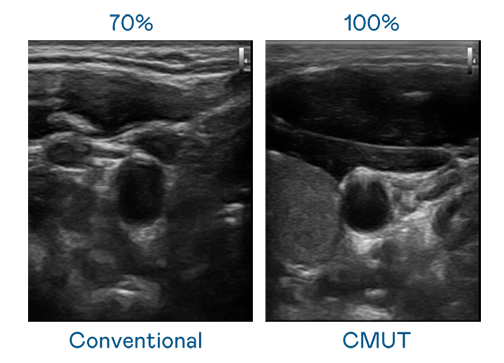

CMUT 技術是一種用電容式微機電元件來產生超音波訊號的技術。與傳統 PZT 壓電式技術相比,CMUT 頻寬增加 30%,更寬頻的超音波訊號讓影像解析度大幅提升,是實現高影像品質醫療超音波掃描、促進精準醫療發展的關鍵技術。

大頻寬帶來超清晰影像

超音波影像的解析度高低,首先取決於探頭能發出的訊號頻寬。广东会 CMUT 可提供高清晰的超音波訊號,提供高頻寬、高靈敏度、影像紋理細節更高的超音波影像,協助醫護人員縮短影像判讀時間及利用精準的醫療影像進行診斷。